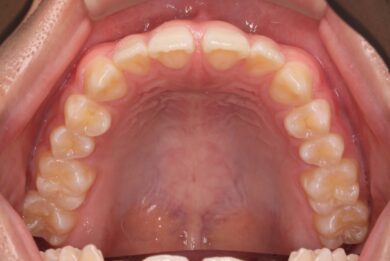

下顎の前歯は通常6本ですが、中央から2番目の歯(側切歯)が左右2本とも欠損している先天性欠如の患者様です。

初診時、下顎だけでなく、上顎の正中(真ん中)にも空隙(隙間)がありました。

初めにマウスピース矯正「インビザライン」による術前矯正を11か月行いました。各隙間を寄せ、インプラントを埋入するスペースを確保し、適切な咬合関係を確立します。

インビザラインの治療計画では、下顎前歯がより美しく審美的に並ぶよう、ご自身の歯とインプラントの歯がほぼ同じ幅径になるよう計算し配列を行いました。

• 治療前